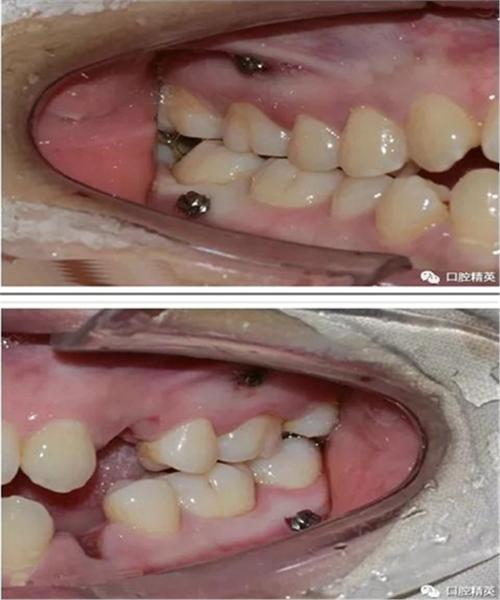

视频的重点环节往往集中在种植钉的植入流程,这部分内容常结合动画演示与实拍画面,清晰呈现每一步操作,术前准备阶段,医生会强调影像学检查(如CBCT)的重要性,以避开牙根、神经血管等解剖结构,确定安全植入位置;同时进行口腔清洁(如洗牙、刮治),确保植入区域无炎症,局部麻醉是关键步骤,视频会展示麻醉药物注射过程,说明麻醉后区域仅感压迫感而无痛感,植入操作中,医生先用微创切口器在牙龈上做小切口(约2-3mm),随后用专用手机备洞(在牙槽骨上制备适合种植钉的窝洞),再将种植旋入窝洞,最后调整露出牙龈部分的高度(约1-2mm,便于后续正畸加力),整个过程通常5-10分钟,创伤小、恢复快。

为帮助患者更直观理解,视频常通过表格对比不同类型种植钉的特点,按植入部位可分为上颌种植钉(如颧骨、腭部、牙槽间隔)和下颌种植钉(如下颌后牙区、颏部),上颌骨骨质较疏松,植入时需注意角度避开上颌窦;下颌骨骨质致密,备洞时可能需要更大扭矩,按材质可分为钛合金种植钉(生物相容性好、强度高,临床应用最广)和不锈钢种植钉(价格较低,但部分患者可能对金属过敏),表格还会列出适用场景,如钛合金种植钉适用于需长期稳定支抗的病例,而不锈钢种植钉多用于短期、简单的牙齿移动控制。